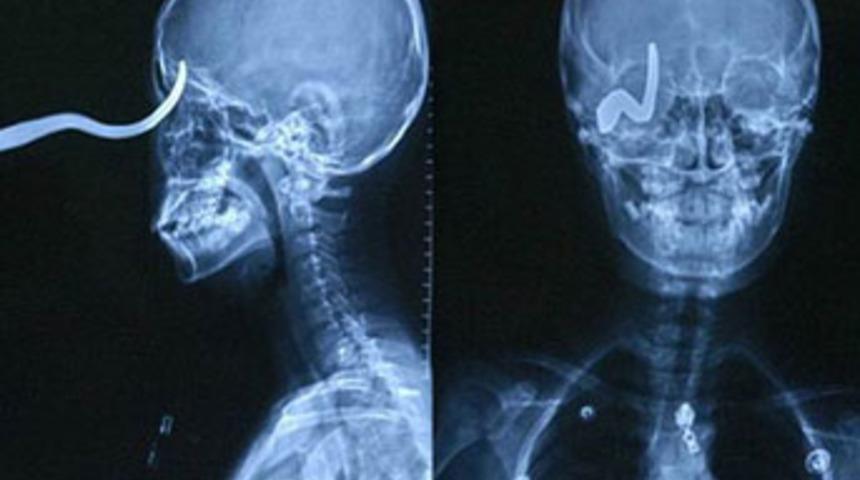

Hemen hastaneye kaldırılan küçük çocuğun kafasına saplanan kancanın, çarpmanın şiddetiyle yana kaydığı ortaya çıktı.

Doktorları, küçük çocuğun kafasındaki kancanın en ufak bir oynamada bile beynine zarar verebileceğini ve çocuğun ölebileceğini açıkladılar.

Sağ gözünü kaybeden Xiaolin'in doktorları, çocuğun hayatta olmasının büyük bir mucize olduğunu belirttiler.